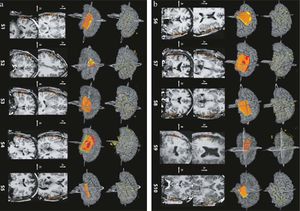

Illustration of a CB-CT and five MR images of the same animal. a) Coronal CB-CT image and (b)-(f) biased field corrected and masked coronal MR images using a T1-weighted (b), T2-weighted (c), ZTE (d), UTE1 (e) and UTE2 (f) sequence. All CB-CT images were first co-registered using 3D Slicer version 3.6.3 by rigid body transformations using normalized mutual information. |